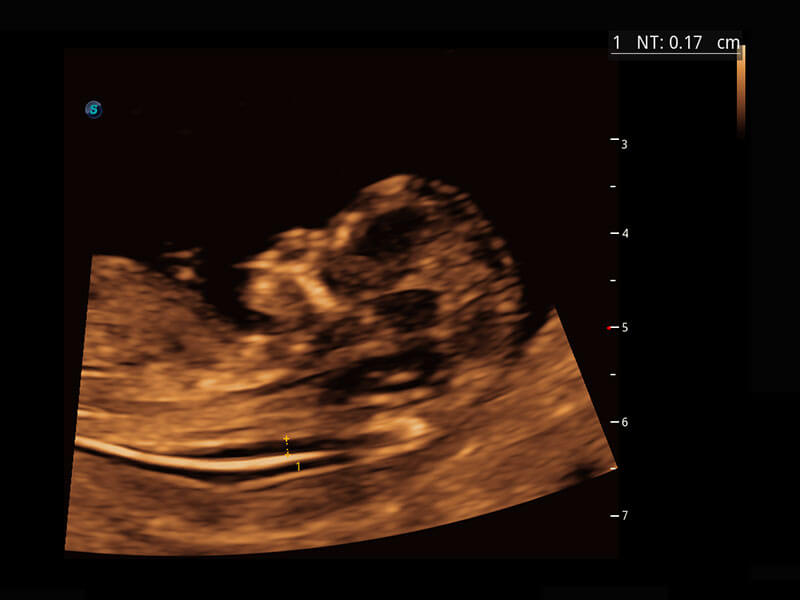

早孕筛查

P60在胎儿早孕期超声筛查中为您带来优异的图像质量。

• 高分辨率容积成像-早孕胎儿